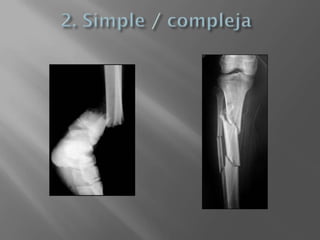

1. Abierta / Cerrada

Transversal  Oblicua  Espiroidea  Conminuta